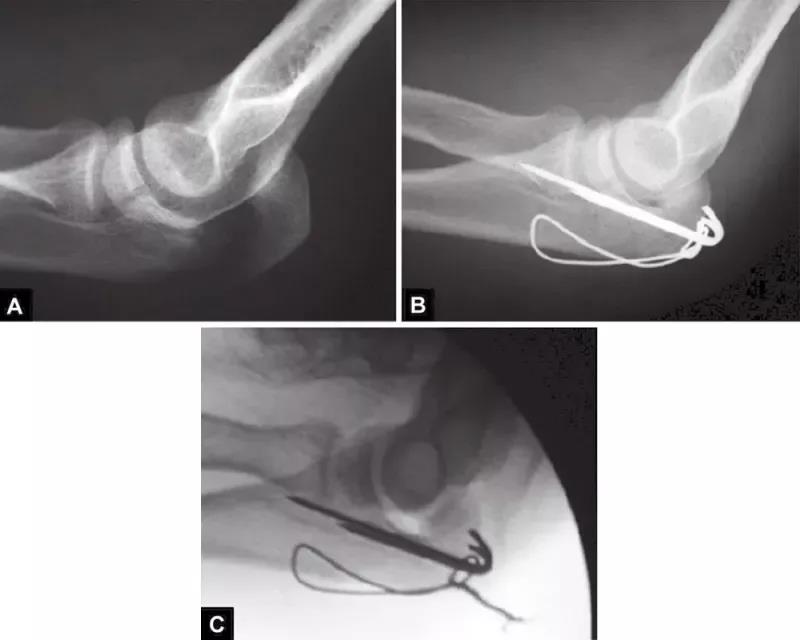

图2A~C关节面部分压缩非常不易觉察。有经验的医生会注意到鹰嘴曲线的变窄从而推断出压缩部分的存在。术中斜位X线片检查压缩骨折仍隐匿,仅在术后的X射线中越来越明显